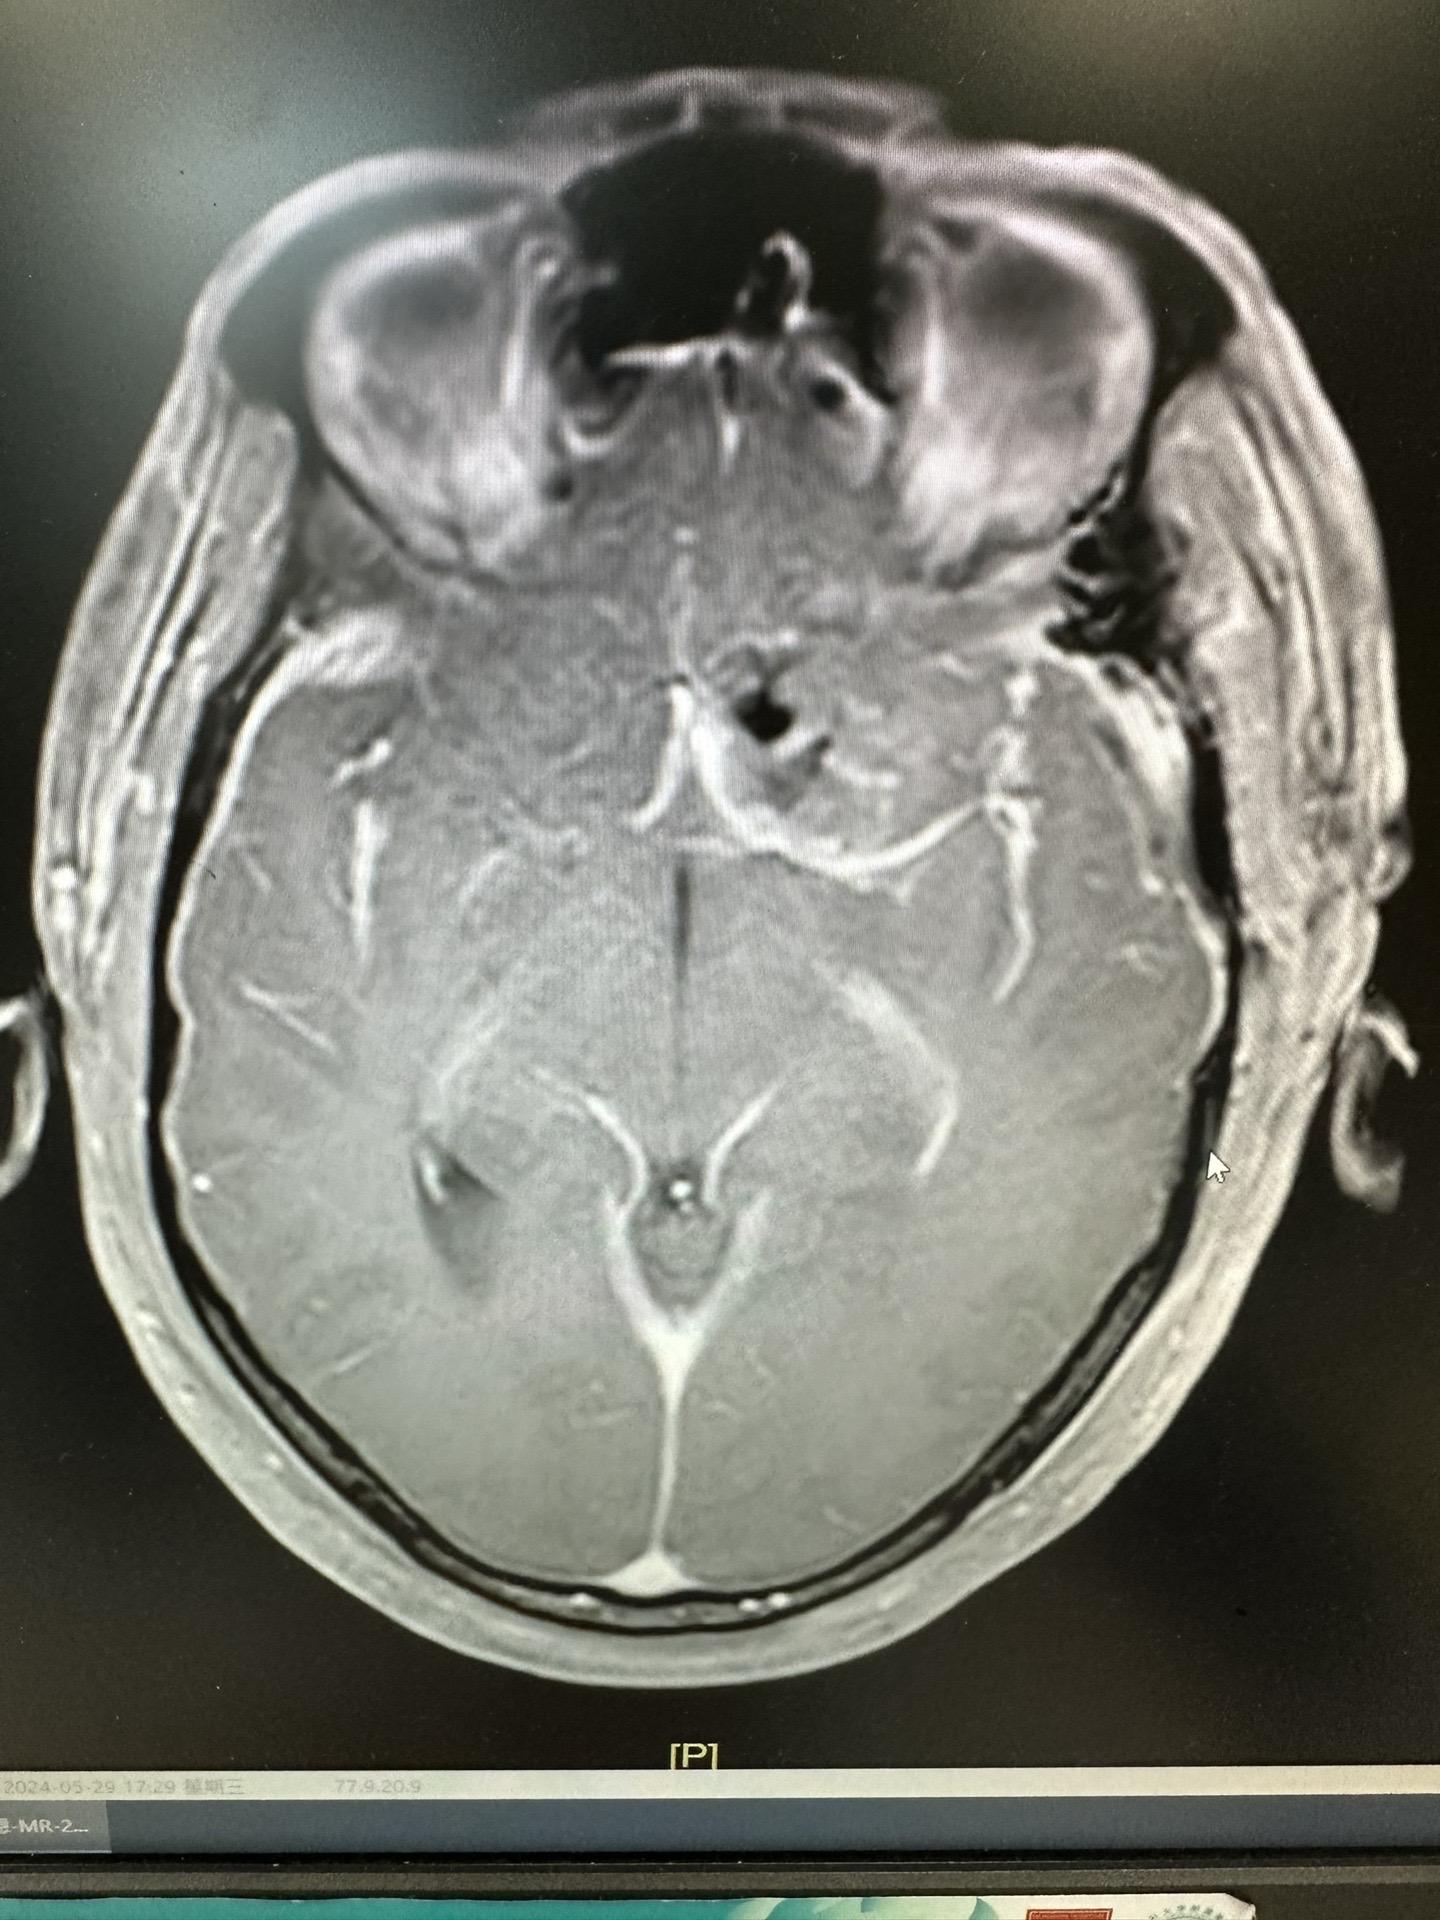

掩盖牙痛的手术。这个肿瘤,周边的重要结构实在太多了,连前交通复合体、内囊前肢、下丘脑、脑室壁、尾状核、中动脉等都一一暴露,如刀尖上行走,手术中导航加持,术中磁共振如同老师一般给你阅卷打分,没想到术中的专注还有意想不到的效果,因为做手术前牙痛,没想到都因为专注做完手术还好了点,看来没入错行,一举两得!